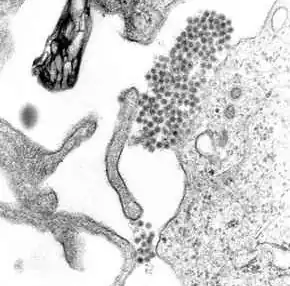

Dengue virus (DENV) is an RNA virus of the family Flaviviridae; genus Flavivirus. Other members of the same genus include yellow fever virus, West Nile virus, and Zika virus. Dengue virus genome (genetic material) contains about 11,000 nucleotide bases, which code for the three structural protein molecules (C, prM and E) that form the virus particle and seven other protein molecules that are required for replication of the virus.[30][31] There are four confirmed strains of the virus, called serotypes, referred to as DENV-1, DENV-2, DENV-3 and DENV-4. The distinctions between the serotypes are based on their antigenicity.[32]

For 2 to 10 days after becoming newly infected, a person's bloodstream will contain a high level of virus particles (the viremic period). A female mosquito that takes a blood meal from the infected host then propagates the virus in the cells lining its gut.[40] Over the next few days, the virus spreads to other tissues including the mosquito's salivary glands and is released into its saliva. Next time the mosquito feeds, the infectious saliva will be injected into the bloodstream of its victim, thus spreading the disease.[41] The virus seems to have no detrimental effect on the mosquito, which remains infected for life.[21]